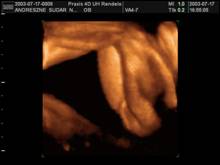

Lábacska